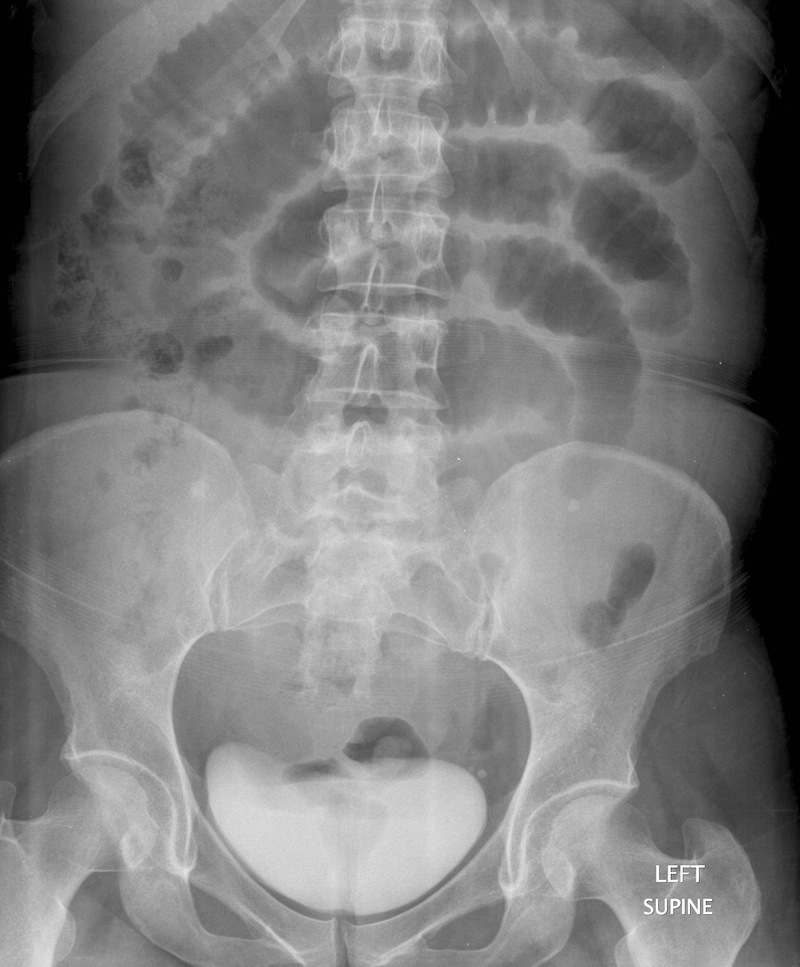

Large bowel obstruction

Coffee bean sign - sigmoid volvulus

twisted on mesentey in LIF

proximal bowel also dilated